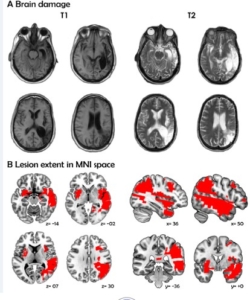

Above and beyond the critical contributions of left perisylvian regions to language, the neural networks supporting pragmatic aspects of verbal communication in native and non-native languages (L1s and L2, respectively) have often been ascribed to the right hemisphere (RH). However, several reports have shown that left-hemisphere activity associated with pragmatic domains (e.g., prosody, indirect speech, figurative language) is comparable to or even greater than that observed in the RH, challenging the proposed putative role of the latter for relevant domains. Against this background, we report on an adult bilingual patient showing preservation of pragmatic verbal skills in both languages (L1: Spanish, L2: English) despite bilateral damage mainly focused on the RH. After two strokes, the patient sustained lesions in several regions previously implicated in pragmatic functions (vast portions of the right fronto-insulo-temporal cortices, the bilateral amygdalae and insular cortices, and the left putamen). Yet, comparison of linguistic and pragmatic skills with matched controls revealed spared performance on multiple relevant tasks in both her L1 and L2. Despite mild difficulties in some aspects of L2 prosody, she showed no deficits in comprehending metaphors and idioms, or understanding indirect speech acts in either language. Basic verbal skills were also preserved in both languages, including verbal auditory discrimination, repetition of words and pseudo-words, cognate processing, grammaticality judgments, equivalent recognition, and word and sentence translation. Taken together, the evidence shows that multiple functions of verbal communication can be widely spared despite extensive damage to the RH, and that claims for a putative relation between pragmatics and the RH may have been overemphasized in the monolingual and bilingual literature. We further discuss the case in light of previous reports of pragmatic and linguistic deficits following brain lesions and address its relation to cognitive compensation in bilingual patients.